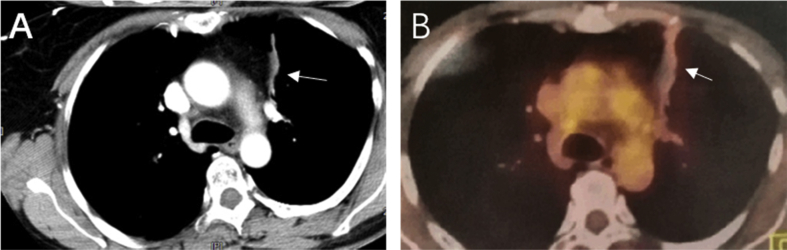

Computed tomography (CT) examination indicated masses in the left upper lung, right upper lung, and the mediastinum with tracheal compression. The right frontal chest wall vein was dilated (Fig. 1 A, B). A biopsy of the upper left lung mass was reported as a poorly differentiated adenocarcinoma. Pathological staging indicated lung adenocarcinoma (Fig. 2), cT4NxM1 (right upper lung with mediastinal lymph node metastasis). The patient was assessed as having unresectable lung cancer. The patient refused systemic chemotherapy. Instead, the patient provided informed consent for bronchial artery infusion chemotherapy.

Fig. 1.

Enhanced CT scan of chest at first visit: (A) soft tissue mass in the left upper lung (→) and enlarged lymph nodes in mediastinum (∗) and (B) right upper lung and mediastinal tumor metastasis (∗), superior vena cava compressed by tumors and right chest wall vein dilatation (→).